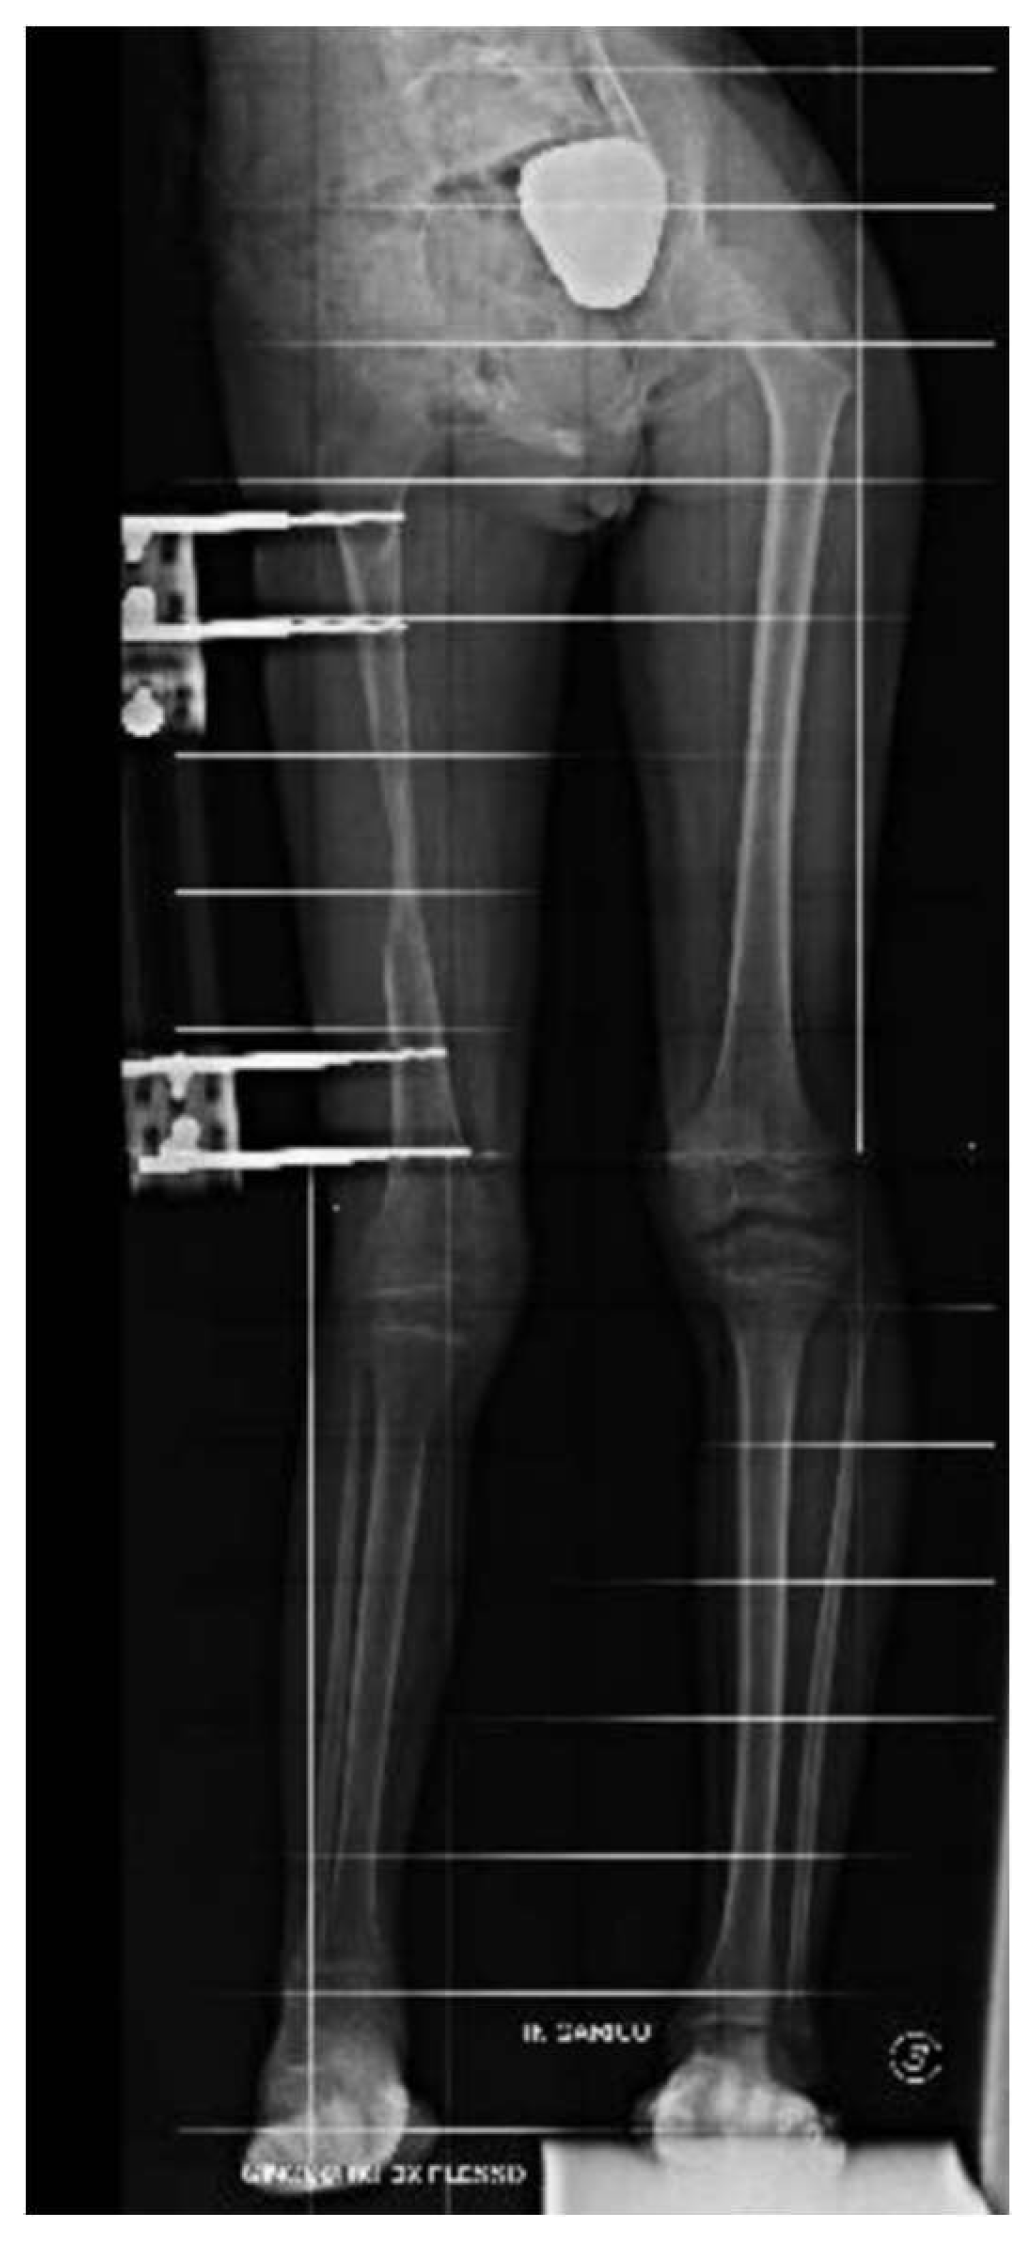

An 8-year-old girl presented to a different hospital with a complaint of leg length discrepancy, right shorter than left. She was brought to local medical attention and promptly diagnosed with congenital femoral deficiency and ipsilateral tibial hypoplasia. At this time, the patient had an acquired leg length discrepancy of 75 mm (femoral 50 mm and tibial 25mm) (Figure 1), she therefore underwent a proximal femoral osteotomy and placement of a LRSTM Orthofix monolateral external fixator to the femur at a different hospital. The procedure was well tolerated with no complications and adequate surgical wound healing. Seven days post-operatively she began the lengthening procedure which consisted of 1/4 turn 4 times per day for a total of 1 mm per day. The patient was followed every two weeks for the first month and then monthly with physical examination and plain film radiographs.

The patient was instructed to start physical therapy for hip and knee range of motion immediately after surgery, while progressive weight-bearing was commenced on the last day of lengthening. At 12 weeks the lengthening goal, 60 mm, was achieved. At 5-months follow up, lower-limb weight-bearing plain radiographs demonstrated that the right femur was within 5 mm of length of the left femur and bone regeneration was visible in the osteotomy gap, however, the study was limited by the inability to fully extend the right knee (Figure 2). Lateral projection radiographs of the right knee showed posterior subluxation of the tibia with respect to the femoral condyles (Figure 3). No action was taken at the time.

Figure 2. caption.